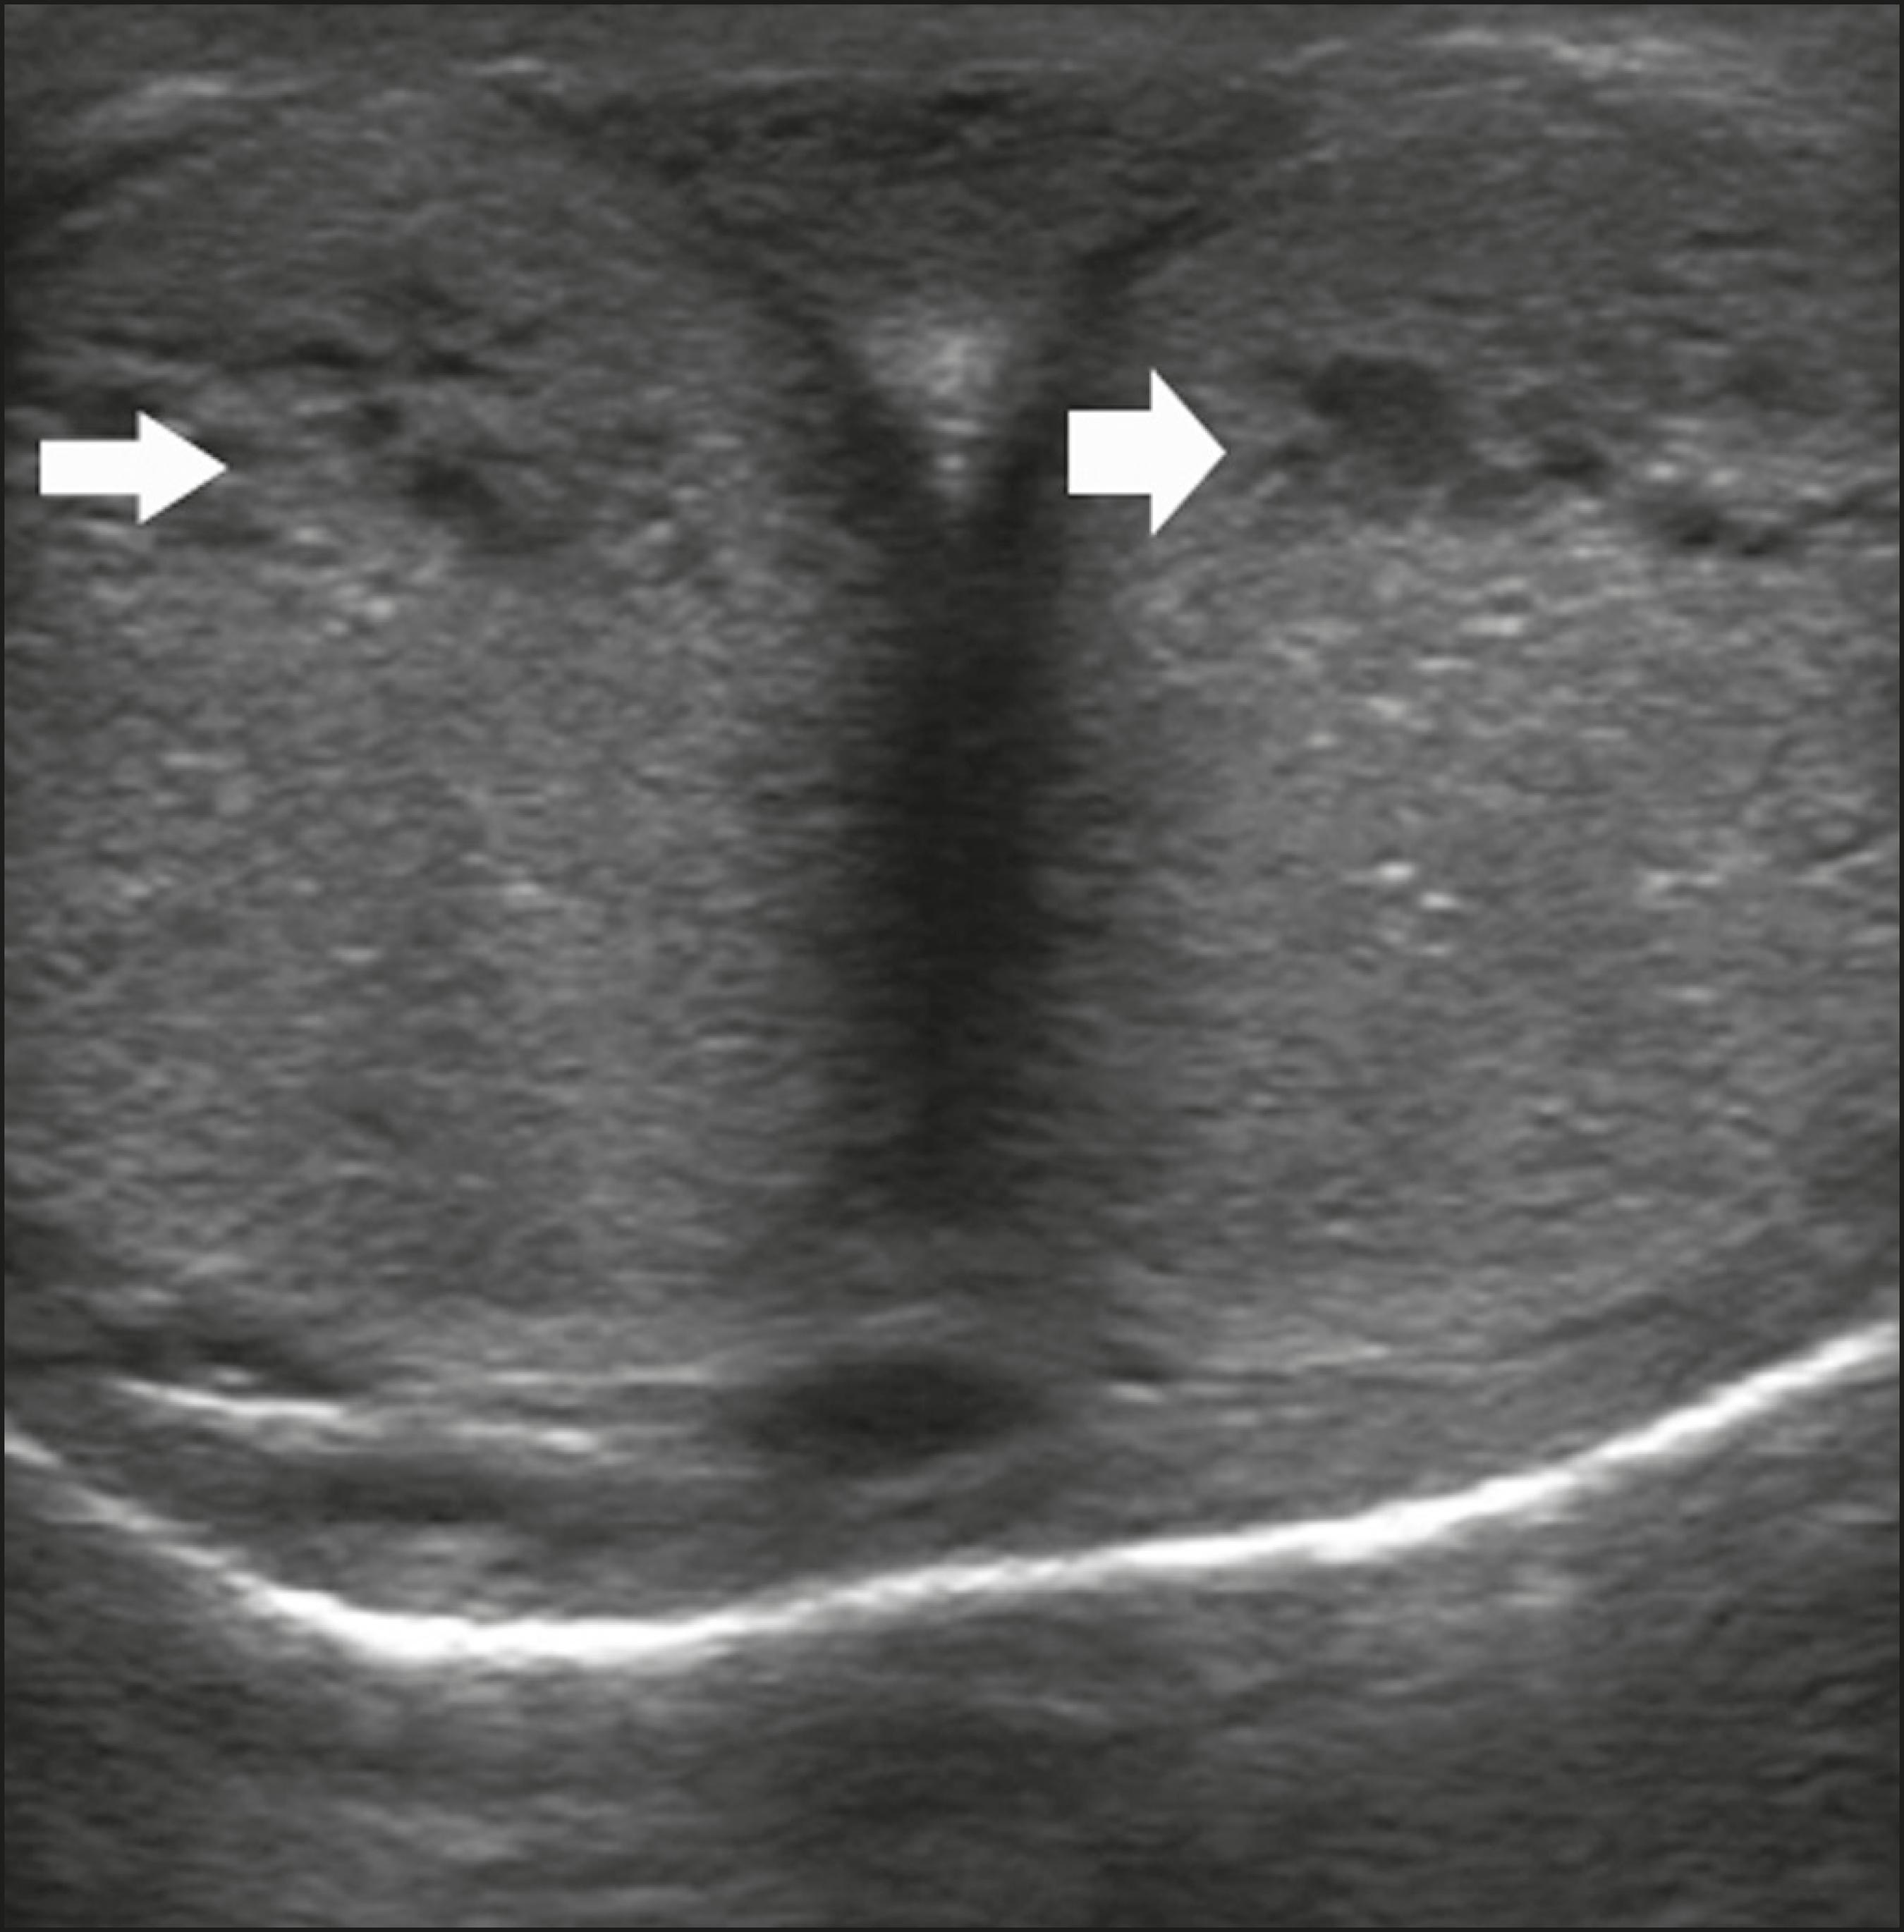

도플러 초음파를 이용한 음경 초음파 검사는 발기된 음경의 혈류를 평가하는 데 사용된다. 기질성 발기부전의 대부분은 해면체 내 혈류 변화와 관련 있으며, 이는 주로 죽상동맥경화증으로 인한 동맥 폐쇄(음경으로의 혈류 감소) 또는 정맥 폐쇄 기전의 실패(음경에서 혈액이 과도하게 유출)로 나타난다. 도플러 검사 전 B-모드 초음파를 통해 종양, 섬유성 반, 석회화, 혈종 등을 확인하고 해면체 동맥의 상태를 평가한다.[42]

발기는 보통 프로스타글란딘 E1 10–20 μg을 주사하여 유도하며, 5분 간격으로 25–30분 동안 동맥 혈류를 평가한다. 프로스타글란딘 E1 사용은 지속발기증 위험이 있는 경우(예: 겸형 적혈구 빈혈증 환자), 음경의 해부학적 기형, 음경 임플란트가 있는 경우 금기이다. 펜톨라민(2 mg)이 추가되기도 하며, 시각적 및 촉각적 자극이 더 나은 결과를 유도한다. 일부에서는 경구용 실데나필을 대체 약물로 권장하기도 하지만 효과는 논란이 있다.[42]

주사 전 혈류는 단상성이며 수축기 속도가 낮고 확장기 혈류가 없으나, 주사 후에는 수축기 및 확장기 최고 속도가 증가한다. 이후 정맥 폐쇄가 일어나며 혈류 속도는 점차 감소하고, 음경이 경직되면 확장기 혈류는 음수가 된다. 수축기 최고 속도(PSV)의 정상 기준은 연구마다 다르나(> 25 cm/s ~ > 35 cm/s), 일반적으로 35 cm/s 이상이면 동맥 기능이 정상, 25 cm/s 미만이면 동맥 부전, 그 사이 값은 불확실한 것으로 간주된다. PSV가 정상이면 최종 확장기 속도(EDV)를 평가하며, 5 cm/s 이상이면 정맥성 발기부전을 시사한다.[42] 측정된 데이터는 관찰된 발기 정도와 연관지어 해석해야 한다.